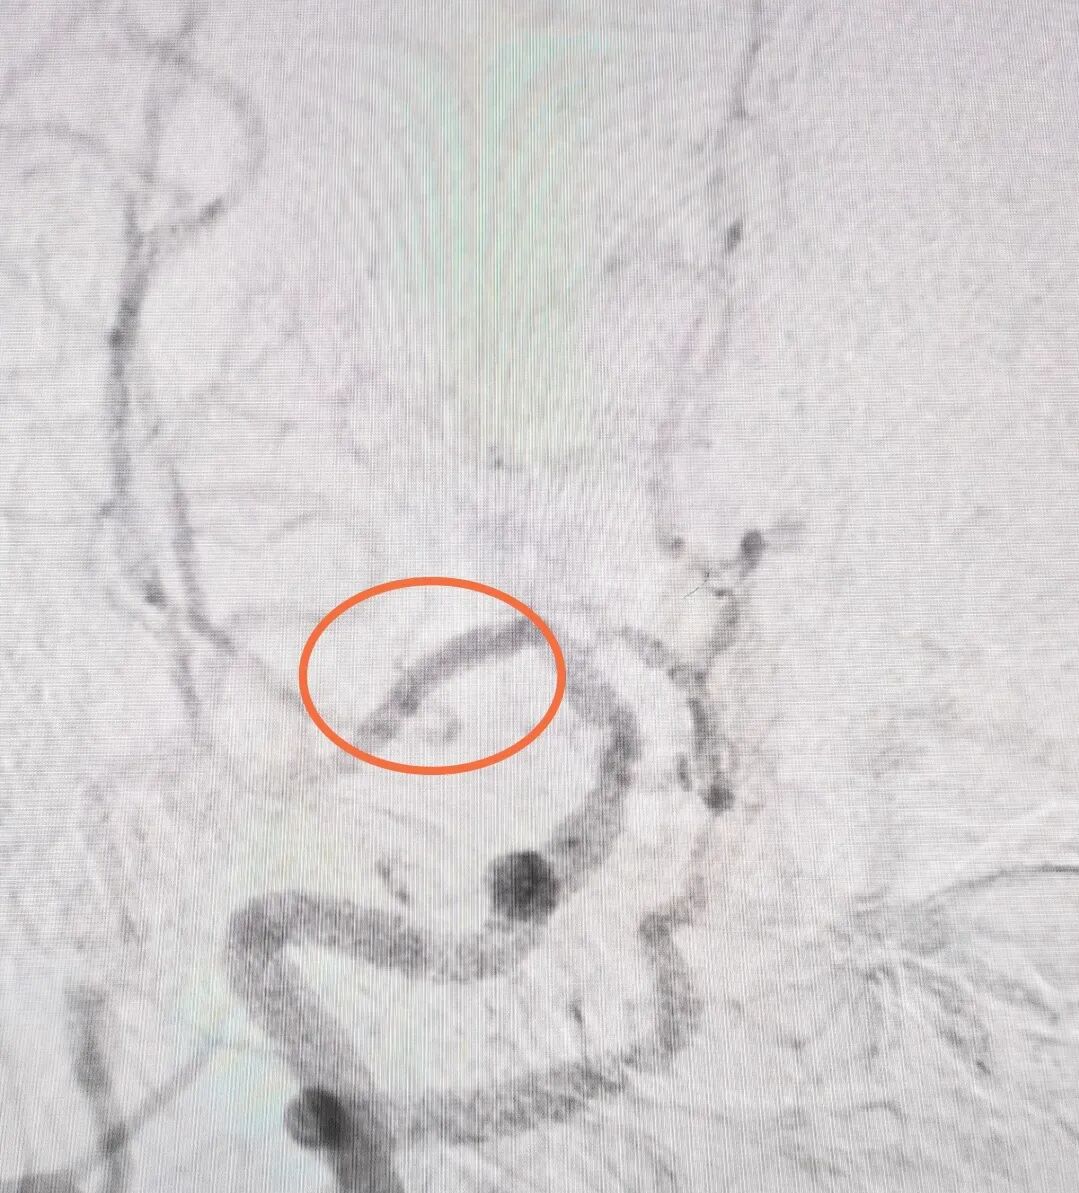

图1:CTA显示重度狭窄的血管;

图2:造影提示斑块已经消失;

术中发现,刘姨右侧大脑中动脉M1段轻度狭窄,由入院时的重度狭窄,到第二天检查时的中度狭窄80%,到现在的血栓消失,溶栓治疗的及时有效,成功避免刘姨脑血管的大面积梗死!

造影提示:刘姨左侧颈内动脉C7段动脉瘤样扩张,约3.5mm*2.5mm(小型动脉瘤)。C7段是颈内动脉的终末段,它紧接着就分叉为大脑中动脉和大脑前动脉,这是颅内动脉瘤的好发部位。

C7段动脉瘤位置示意